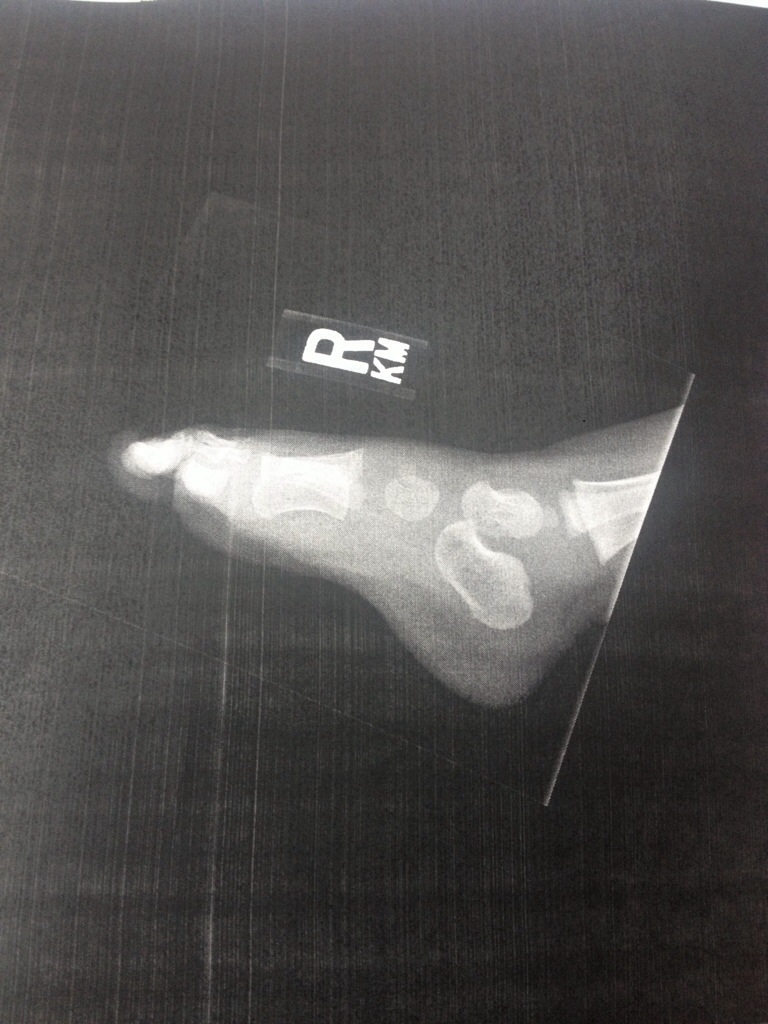

A few weeks ago, josh was leaving for a road bike ride. Jacob was sad, so josh lifted him onto the bike for a quick ride, as he has done on his each cruiser. But this time, Jacob stuck his foot down in between the wheel and frame and hurt himself. He seemed to be okay, but time passed and he started yelling “owie!” And telling us he had a boo-boo on that foot. I took him to the doctor and they determined it was just a sprain (and that “owie” is his favorite new word).

But look at how few bones he has in his tiny foot?!